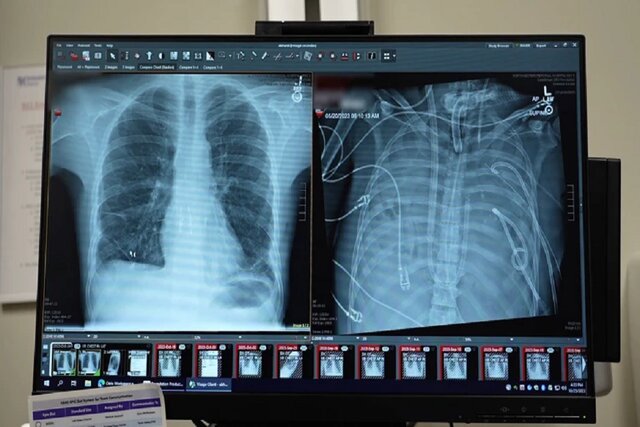

قبل از قرار گرفتن روی سیستم ریه مصنوعی، این مرد دچار سندرم حاد دیسترس تنفسی شده بود که یک وضعیت اغلب تهدیدکننده حیات است که در آن ریهها نمیتوانند اکسیژن کافی جذب کنند و این مشکل توسط ویروس آنفلوانزا ایجاد شده بود. سپس او روی ونتیلاتور قرار گرفت، اما دچار عفونت مقاوم به دارو شد. این عفونت باعث شد قسمتهایی از ریههای او پر از چرک شود و او وارد شوک سپتیک شود که در این مرحله قلب و کلیههایش شروع به از کار افتادن کردند.

به طور شگفتانگیز، مرد شروع به بهبود سریع کرد. در عرض ۴۸ ساعت، او همه داروها برای حمایت از فشار خون را کنار گذاشت، عملکرد کلیه او کاملا بازیابی شد و قلب او به طور طبیعی کار میکرد. در این مرحله، مرد پیوند دو ریه را دریافت کرد و سالها بعد هیچ نشانهای از رد عضو یا اختلال عملکرد ریه نشان نداد. اکنون تقریبا سه سال از انجام این کار گذشته است و حال بیمار واقعا خوب است.